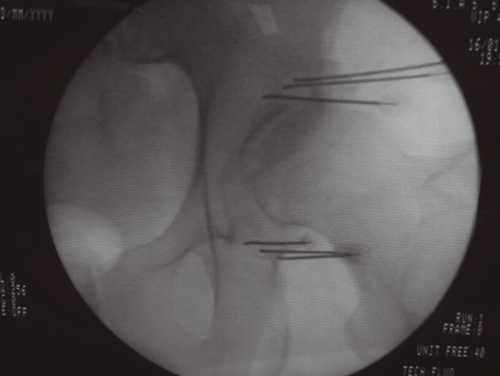

El dolor osteomuscular es la causa más frecuente de consulta en las unidades del dolor; la degeneración artrósica es la patología más prevalente dentro del dolor osteomuscular, siendo las zonas más afectadas la columna vertebral (tanto a nivel lumbar como cervical), las extremidades (rodilla, cadera, hombro), quedando el resto de las articulaciones de la anatomía como localizaciones menos frecuentes. Las técnicas intervencionistas intentan paliar el dolor causado por la artrosis, en muchos casos en pacientes con patología acompañante que hace que la posible solución quirúrgica sea descartada por su excesivo riesgo (prótesis de rodilla o cadera), o bien, como ocurre en el caso de la espondiloartrosis, el tratamiento quirúrgico no garantice la eliminación del dolor, como ocurre con la artrodesis de columna preconizada para tratar este tipo de dolor. Como siempre, la dificultad estriba en poder ofrecer al paciente un tratamiento con evidencia científica suficiente y con el riesgo más bajo posible, que conlleve a un resultado satisfactorio para él. El presente artículo pretende revisar las técnicas intervencionistas disponibles para tratar el dolor causado por la artrosis, y su grado de evidencia cuando esta está disponible.